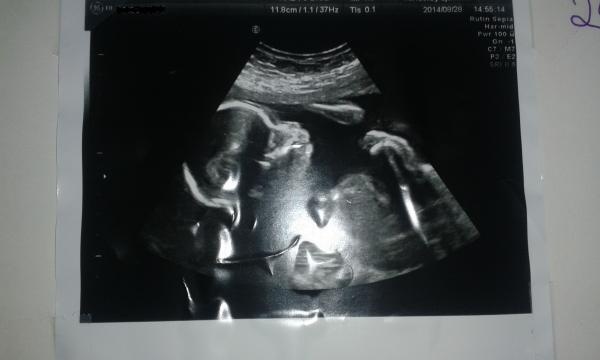

Bild ifrån vecka 19. Inne i rummet med mig och min kompis så fanns tre andra läkare. Bara för att se om fostret lever. Här konstaterade man att mitt beräknande datum är 21 Januari och att bäbis är full av liv. Vi vet inte kön (faktiskt ganska skönt).